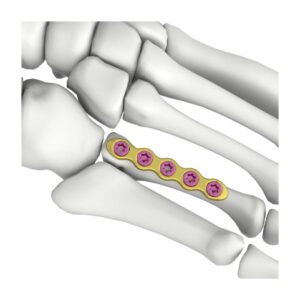

SISTEMA AIMIMINI VAL PARA MANOS 1.5/2.4/2.7 BLOQUEADO

El implante AIMIMINI val hand mini lock system se puede utilizar para la fijación temporal, corrección o estabilización del bloque óseo en la posición anatómica de la mano.